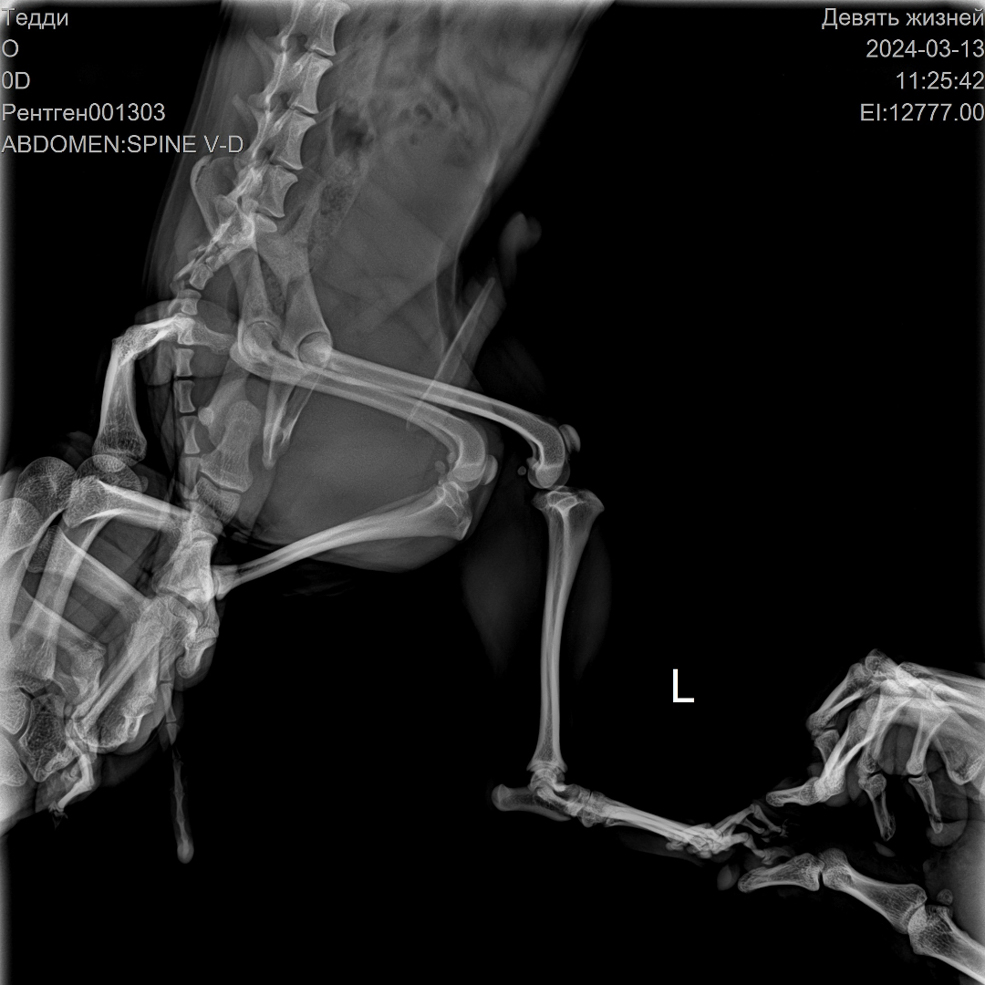

Нас встретил сотрудник Кирилл. Он полностью провёл осмотр, сделал рентген – у них есть вариант электронного снимка, когда можно приближать, рассматривать. Оказалось, что все конечности целые.